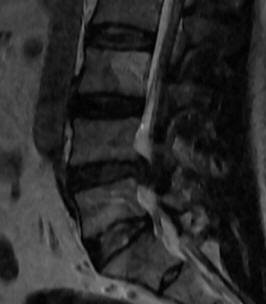

21-DECEMBER-2016  JAAFAR MUHAMED MISLEH 43 YEARS  HUGE EXTRUDED DISK L4-5 WITH LEFT FORAMINAL OCCLUSION.

The patient came to the clinic 20-December-2016 complaining of LBP for 20 years with left sciatica for 2 months with numbness of all toes left foot. MRI lumbar spine performed 14-December-2016 showing huge extruded disc L4-5 with left foraminal occlusion and downward migration. The patient tried all alternative methods of treatment and failed.

The extruded disc L4-5  in sagittal and axial views.